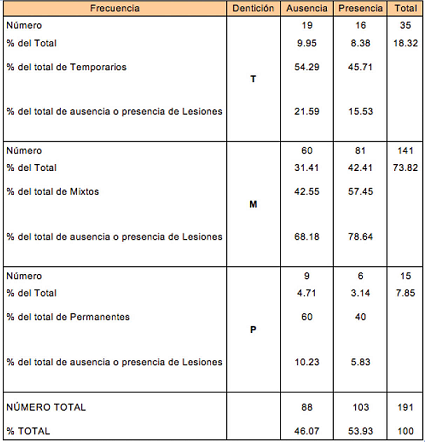

La Figura 3 muestra el porcentaje de sujetos en la muestra según su tipo de dentición.

La Tabla 2 presenta información sobre el tipo de dentición y su asociación con la presencia o ausencia de alguna lesión. La ausencia/presencia de lesiones resulto estadísticamente independiente del tipo de dentición: temporaria (T), mixta (M) y permanente (P) (Chi-cuadrado= 2.8242, valor-p = 0.2436).

Considerando el tipo de dentición del sujeto, se vio que Morsicatio buccarum fue la lesión más frecuente en los tres tipos de dentición (T = 43%, M = 52% y P = 20%), observándose diferencias significativas Chi-cuadrado=6,2136 , valor-p = 0,0447*.

Tabla 2: Ausencia/Presencia de lesiones por tipos de dentición (T= temporaria, M= mixta, P= permanente).